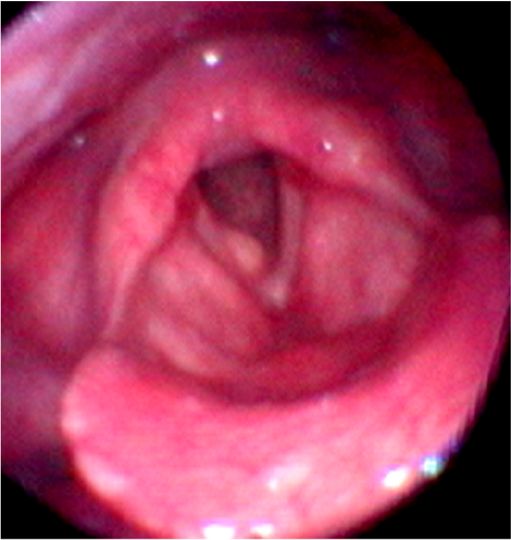

・声帯ポリープは声帯結節、声帯ポリープ、ポリープ様声帯の3種類にわけられます。

・声帯ポリープは成人の男女にみられ、通常、片側性で声を酷使する職業の人に発生します。